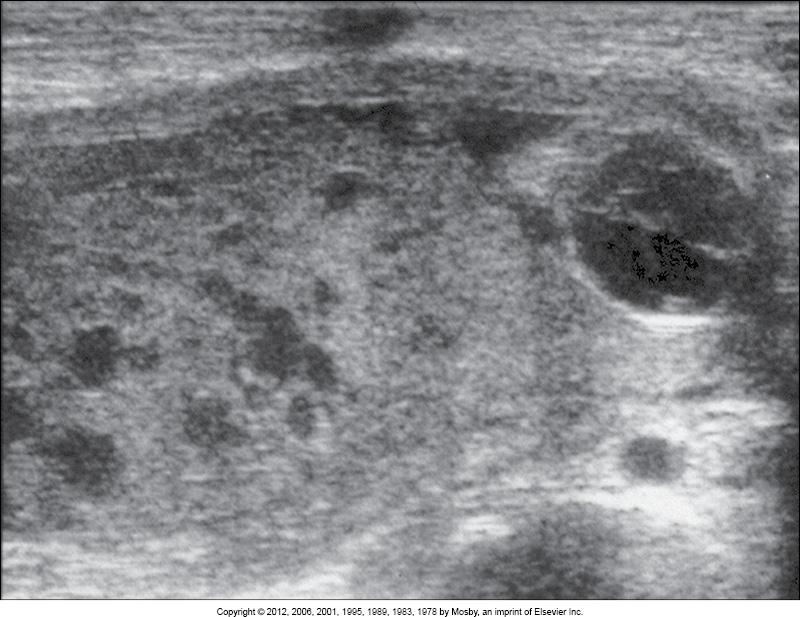

what does this image show?

intervillous thrombosis